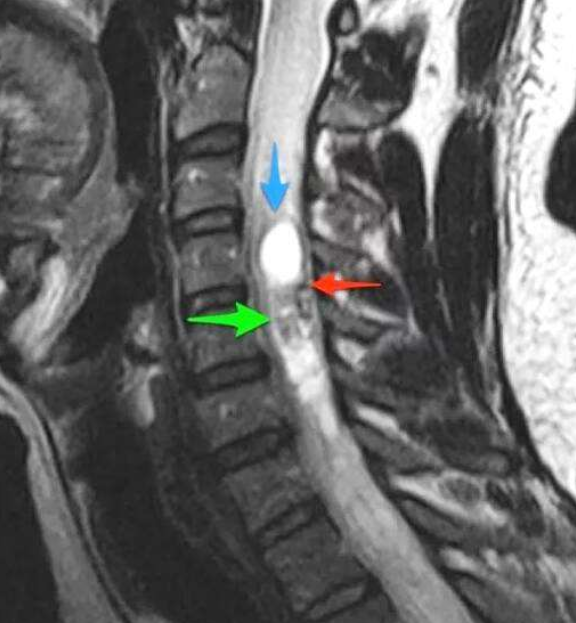

根據(jù)脊髓腫瘤的位置,一般又分為髓內(nèi)腫瘤和髓外腫瘤:

脊髓腫瘤影像學(xué)圖

髓內(nèi)-髓外-腫瘤位于脊髓的薄層(硬腦膜)內(nèi),但在實(shí)際的脊髓外。在這個(gè)地方發(fā)生的頻率是40%。較常見的這些類型的腫瘤發(fā)生在脊髓的蛛網(wǎng)膜(腦膜瘤)、從脊髓延伸出的神經(jīng)根(神經(jīng)鞘瘤和神經(jīng)纖維瘤)或脊髓基底(終絲室管膜瘤)。雖然腦膜瘤通常是良性的,但它們很難切除并可能復(fù)發(fā)。神經(jīng)根腫瘤通常也是良性的,盡管神經(jīng)纖維瘤隨著時(shí)間的推移可能變成惡性的。脊髓末端的室管膜瘤可能很大,該區(qū)域細(xì)致的神經(jīng)結(jié)構(gòu)的微妙特性可能使切除變得困難。

髓內(nèi)-這些腫瘤生長在脊髓內(nèi)。它們通常來源于神經(jīng)膠質(zhì)細(xì)胞或室管膜細(xì)胞(一種神經(jīng)膠質(zhì)細(xì)胞),這些細(xì)胞遍布于脊髓的間質(zhì)。在這個(gè)地方發(fā)生的頻率大約是5%。星形細(xì)胞瘤和室管膜瘤是較常見的兩種類型。星形細(xì)胞瘤多見于胸段,其次為頸段。室管膜瘤較常見于絲(脊髓底部),其次是頸段。它們通常是良性的(與顱內(nèi)相比),但是很難切除。

硬膜外-腫瘤位于硬腦膜外,硬腦膜是圍繞脊髓的一層薄薄的覆蓋物。該地區(qū)與上述地區(qū)的發(fā)生率約為55%。這些病變通常是由于轉(zhuǎn)移性癌癥或較少見的神經(jīng)鞘瘤來自覆蓋神經(jīng)根的細(xì)胞。有時(shí),硬膜外腫瘤通過椎間孔,部分位于椎管內(nèi),部分位于椎管外。